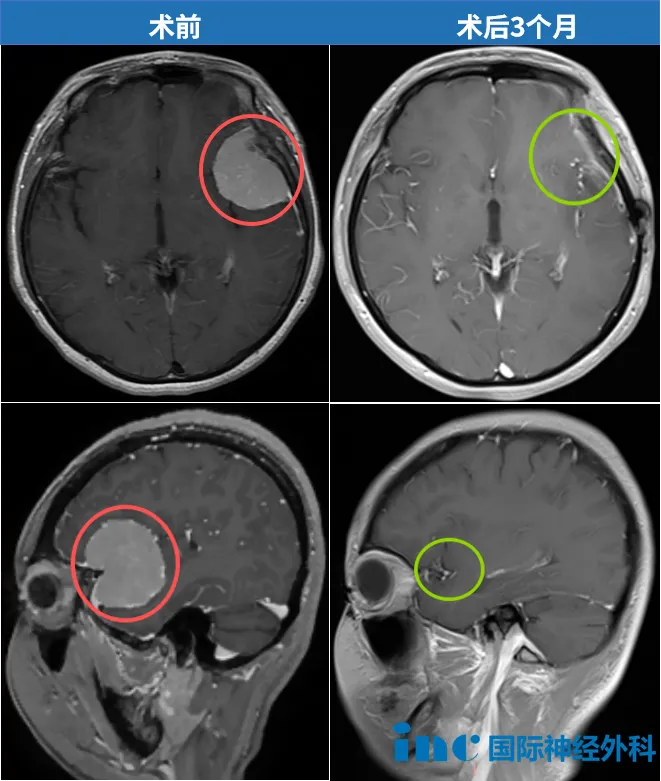

病灶現(xiàn)在已經(jīng)不存在了。影像上沒(méi)有任何腫瘤殘留,也沒(méi)有復(fù)發(fā),一切都如預(yù)期般良好,她現(xiàn)在不需要任何輔助治療。 開(kāi)顱術(shù)后3個(gè)月,我收到了INC巴特朗菲教授的術(shù)后隨訪報(bào)告。最讓我激動(dòng)的是,教授還在報(bào)告上用中文寫了四個(gè)字:不能更好。這一刻我知道,這場(chǎng)與腦膜瘤的抗?fàn)?,我贏了。 38歲的我經(jīng)營(yíng)...

“病灶現(xiàn)在已經(jīng)不存在了。影像上沒(méi)有任何腫瘤殘留,也沒(méi)有復(fù)發(fā),一切都如預(yù)期般良好,她現(xiàn)在不需要任何輔助治療。”

開(kāi)顱術(shù)后3個(gè)月,我收到了INC巴特朗菲教授的術(shù)后隨訪報(bào)告。最讓我激動(dòng)的是,教授還在報(bào)告上用中文寫了四個(gè)字:“不能更好”。這一刻我知道,這場(chǎng)與腦膜瘤的抗?fàn)帲亿A了。

“說(shuō)話完全沒(méi)問(wèn)題,手腳活動(dòng)也正常,精神狀態(tài)比想象中好太多了!”當(dāng)巴特朗菲教授親自查房,確認(rèn)腫瘤已完全切除時(shí),我激動(dòng)不已——我知道,自己做出了人生中正確的選擇。